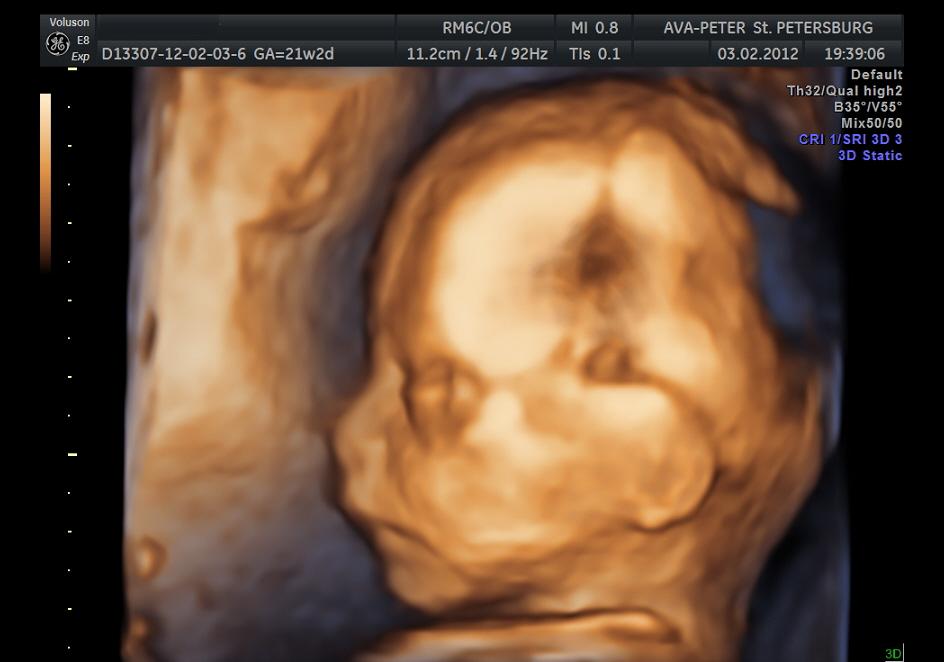

3D-УЗИ

Методика, позволяющая получить трехмерное изображение еще не рожденного ребенка, является дополнительной. Опытный специалист может выявить аномалии развития и в ходе «обычного» УЗИ. На 3D-картинке можно подробно рассмотреть только внешний вид плода, а состояние его органов и систем оценить нельзя. В редких случаях именно трехмерная картинка позволяет выявить такие аномалии, как «заячья губа» (расщепление верней губы на фоне незаращения неба) или полидактилия (анатомическое отклонение, при котором на конечности более 5 пальцев).

3D-УЗИ в большей степени интересно родителям, поскольку получает возможность получить и сохранить на цифровом носителе изображении, близкое к цифровому фотоснимку. То же касается и 4D, причем, чтобы рассмотреть мимику и движения будущего ребенка матери предстоит исследование продолжительностью до 1 часа и более.